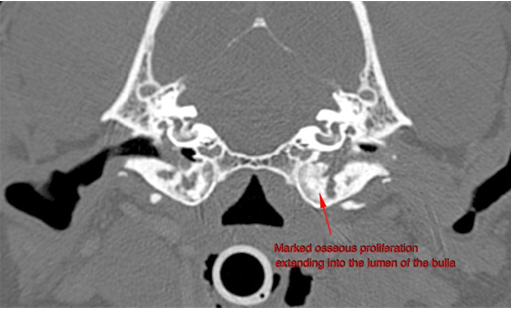

What can be seen here?

CT (X-ray computed tomography)

Can see bony changes after chronic pseudomonas otitis